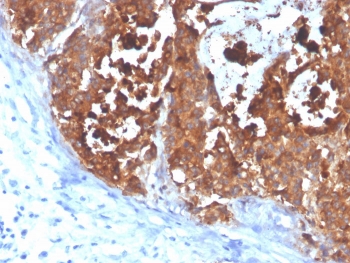

IHC staining of FFPE human colon carcinoma with CEA antibody (clone C66/4098). HIER: boil tissue sections in pH 9 10mM Tris with 1mM EDTA for 20 min and allow to cool before testing.

Applications Immunohistochemistry (FFPE) : 1-2ug/ml for 30 minutes at RT